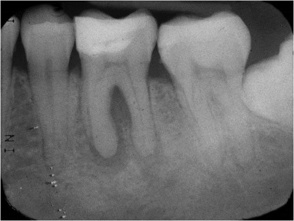

Endodontic-periodontal (endo-perio) lesions occur as a result of a pathologic communication between the pulpal and periodontal tissues (see figure: Endo-perio lesion).

A periapical radiograph taken using the long cone paralleling technique shows tooth 36 with a endo-perio lesion involving both root apices and the furcation, mild horizontal bone loss of less than 10% of root length and a mesially impacted 38.